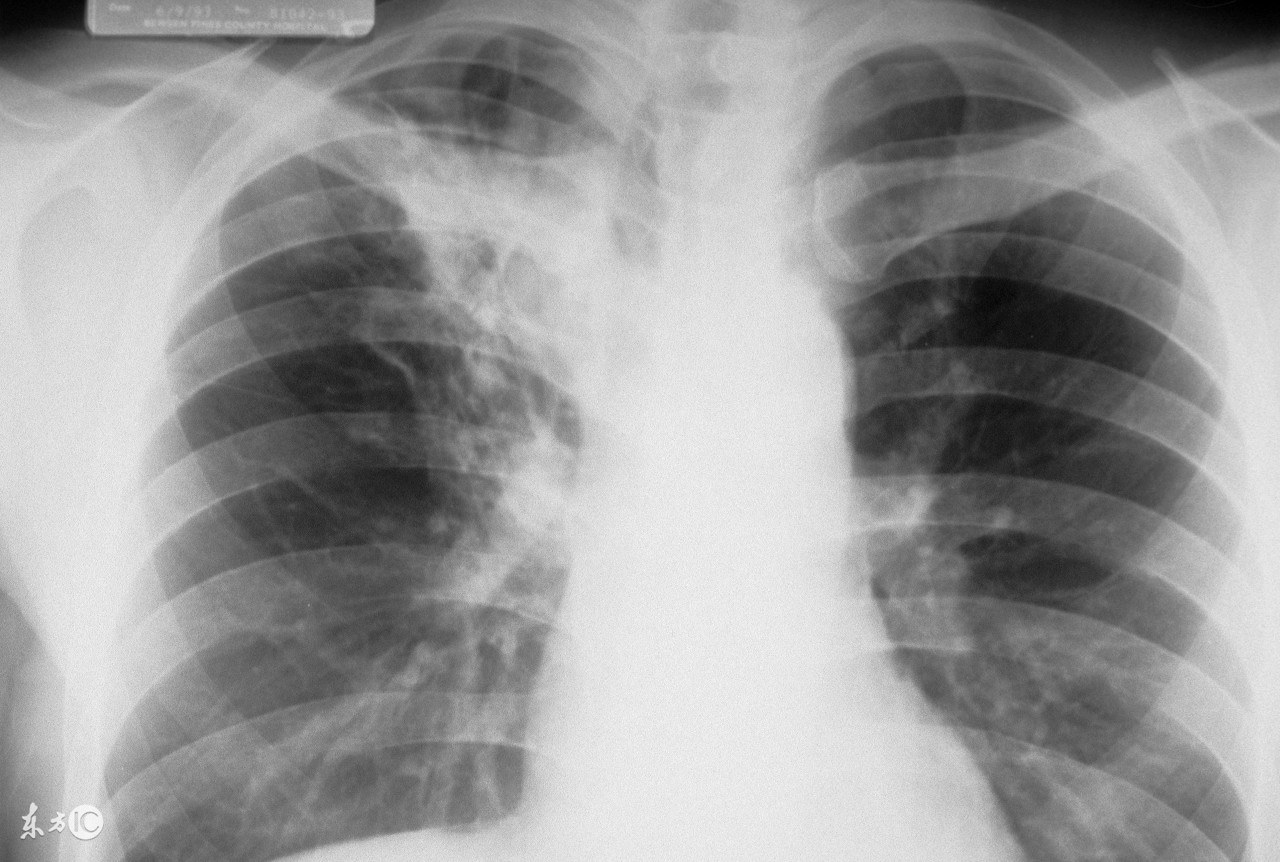

被怀疑有肺结核 (无意检查出肺结核)

为了更准确的诊断肺结核,一般都要做肺结核皮试,通过做这个检查可以明确人体带菌的概率,肺结核皮试出现双圈是什么意思?阳性和阴性有什么不同?